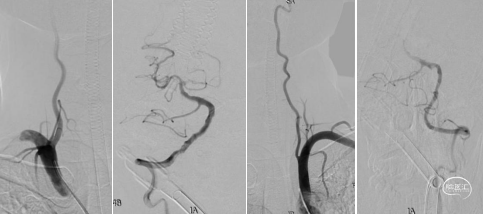

一次取栓实现血管再通,复查造影提示R-M1局限性狭窄,观察20分钟复查造影R-M1局限性狭窄无明显回缩,前向血流III级,因前向血流速度正常,故原位狭窄暂不同期处理,待病情稳定后择期处理。

1.该患者右侧大脑中动脉闭塞,根据取栓支架释放后造影情况,判断为ICAS病变基础上继发急性闭塞,血栓负荷量不大,SWIM技术一次取栓实现血管再通,再次造影证实R-M1段狭窄,经过动态观察,血管狭窄无明显变化,前向血流III级,维持良好,故未进一步行球囊扩张或支架置入。